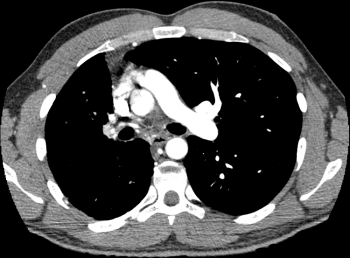

This patient has chronic TB. Diagnosis?

Rasmussen aneurysm- a rare complication of pulmonary TB that can cause massive hemoptysis.

It is a pulmonary artery pseudoaneurysm which develops as a result of direct continuity with the fibrocaseous TB infection, get direct invasion of the artery wall (versus typical mycotic aneurysm caused by septic emboli).